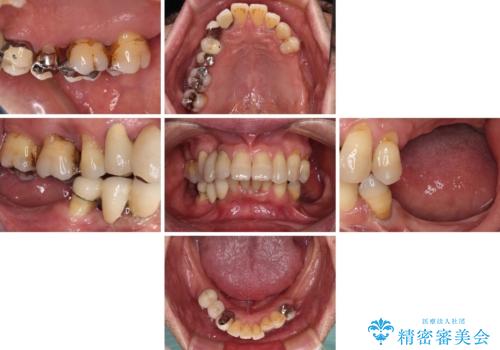

- 以前入れ歯を製作したものの、装着感が悪く使用できなかったとのことで来院された患者様です。

インプラントによる治療プランも提案しましたが、インプラントは避けたいとのご希望であったため、入れ歯による補綴治療を行うこととしました。

自費治療の義歯は装着感がとても良いですが、急に入れ歯を装着すると、異物感が強く継続使用できなくなるため、仮歯の期間中に保険治療での義歯を装着してもらい、口腔内を義歯に慣れさせるようにしました。

より適合の良い義歯とするため、セラミッククラウンなどは義歯の設計に合わせた土台の歯となるよう全て再製作をし、安定感に優れた義歯を製作することができました。